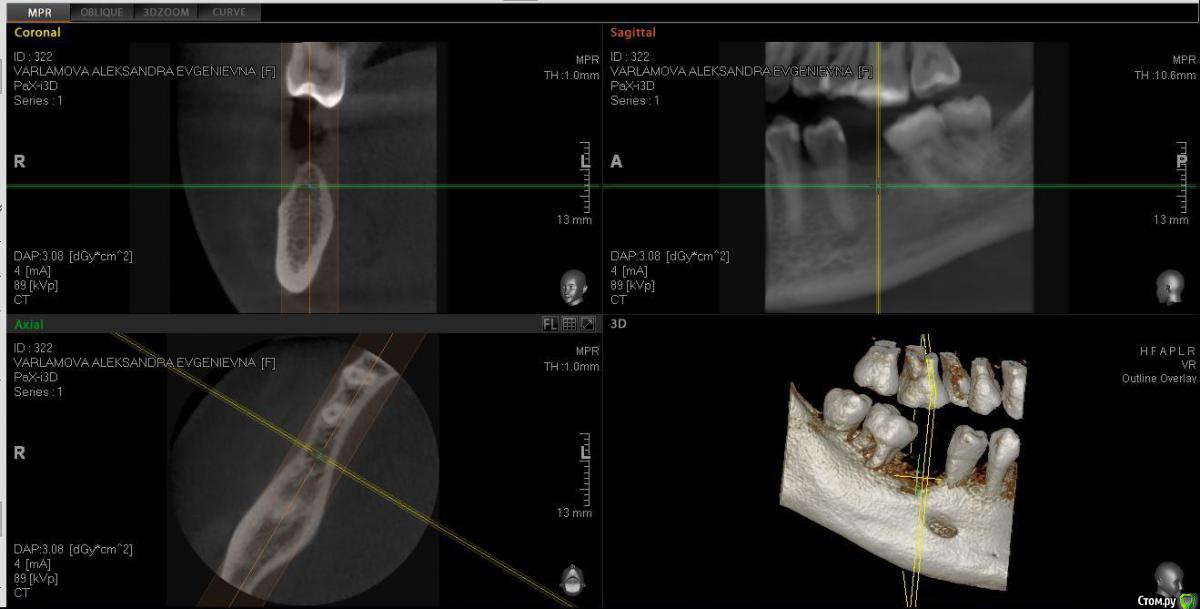

Александра_85 Опубликовано 12 марта, 2015 Поделиться Опубликовано 12 марта, 2015 (изменено) Здравствуйте, собираюсь сделать имплантацию 6 нижнего зуба справа.Удален этот зуб был 4 года назад, кость довольно сильно ушла.Мой имплантолог советует кость не наращивать, и установить тонкий импрант АльфаБио.Хотелось бы услышать ваше мнение.Во вложении ортопантограмма годичной давности, и свежее КТ по ссылкеhttp://www.fayloobmennik.net/4686662 Я не очень понимаю, как выложить срез.Сделала скрин, может по нему будет понятно Изменено 12 марта, 2015 пользователем Александра_85 Ссылка на комментарий

Александра_85 Опубликовано 12 марта, 2015 Автор Поделиться Опубликовано 12 марта, 2015 качать кт мало кто станет, выкладывайте срезы интересующей области Понятно, у меня получилось сделать скрин, может по нему будет что-то видно Ссылка на комментарий

Александра_85 Опубликовано 12 марта, 2015 Автор Поделиться Опубликовано 12 марта, 2015 да, пожалуйста, ждем снимокВот. Ссылка на комментарий

red_butler Опубликовано 12 марта, 2015 Поделиться Опубликовано 12 марта, 2015 (изменено) Вот.я бы имплантировал с одномоментной костной пластикой, однако существует современная тенденция - ставить импланты малого диаметра и ограничиваться пластикой десны Изменено 12 марта, 2015 пользователем red_butler 1 Ссылка на комментарий